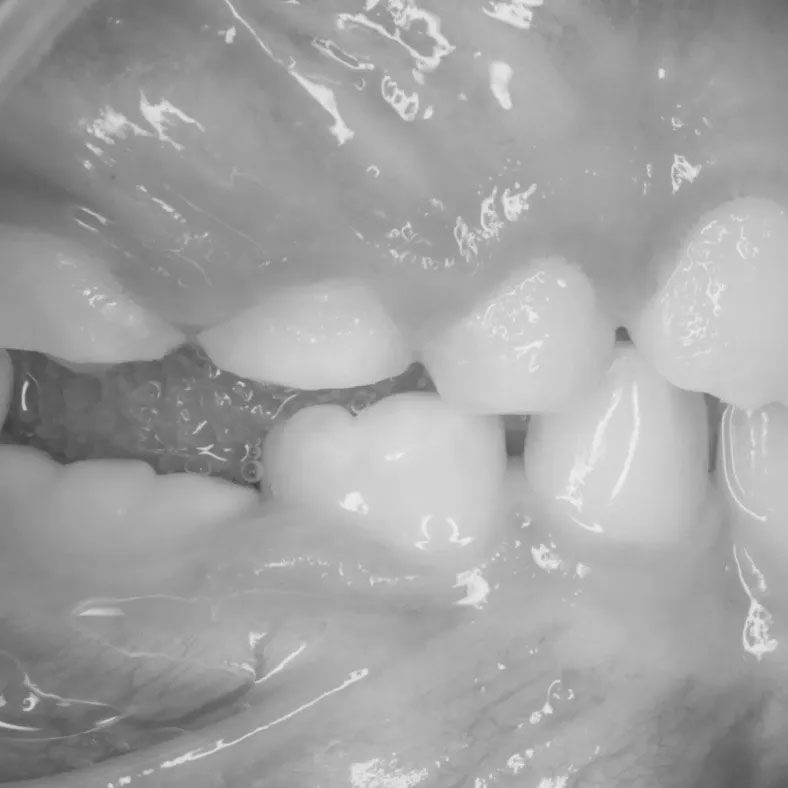

Orthodontic treatments play a significant role in addressing ankylosis. Frequently, an ankylosed tooth is shorter than the teeth next to it, and often ankylosed teeth can appear to be submerging. If adjacent teeth have grown over or tipped over an ankylosed tooth, space can be lost. In these cases, tooth alignment and bites can be compromised. Often orthodontic treatment is required to align the teeth around the ankylosed tooth to allow access for the tooth to be surgically removed. After removing the ankylosed tooth, sometimes the space can be closed, and sometimes the bite relationship will dictate the need to close some of the space, but to leave enough space to restore the missing tooth. These procedures require orthodontic intervention.

Most cases of ankylosis require surgical intervention. If the ankylosed tooth is a primary tooth, surgical extraction is necessary. If the ankylosed tooth is a permanent tooth, crown lengthening is a surgical procedure that may be performed to expose more of the ankylosed tooth’s crown, to allow for restoration of the tooth to be level with the bite. In situations where a permanent ankylosed tooth cannot be effectively treated, extraction may be necessary. After extraction, dental implants can be considered as a means of restoring the missing tooth and improving oral function.